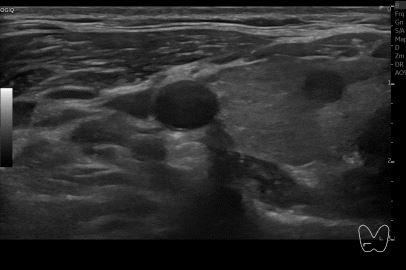

상기환자 외부건진 갑상선 이상소견으로 세침검사위해 내원하신 30대 중반 여성분으로

의심스러운 갑상선 우엽 세포검사후 갑상선암으로 진단되었습니다